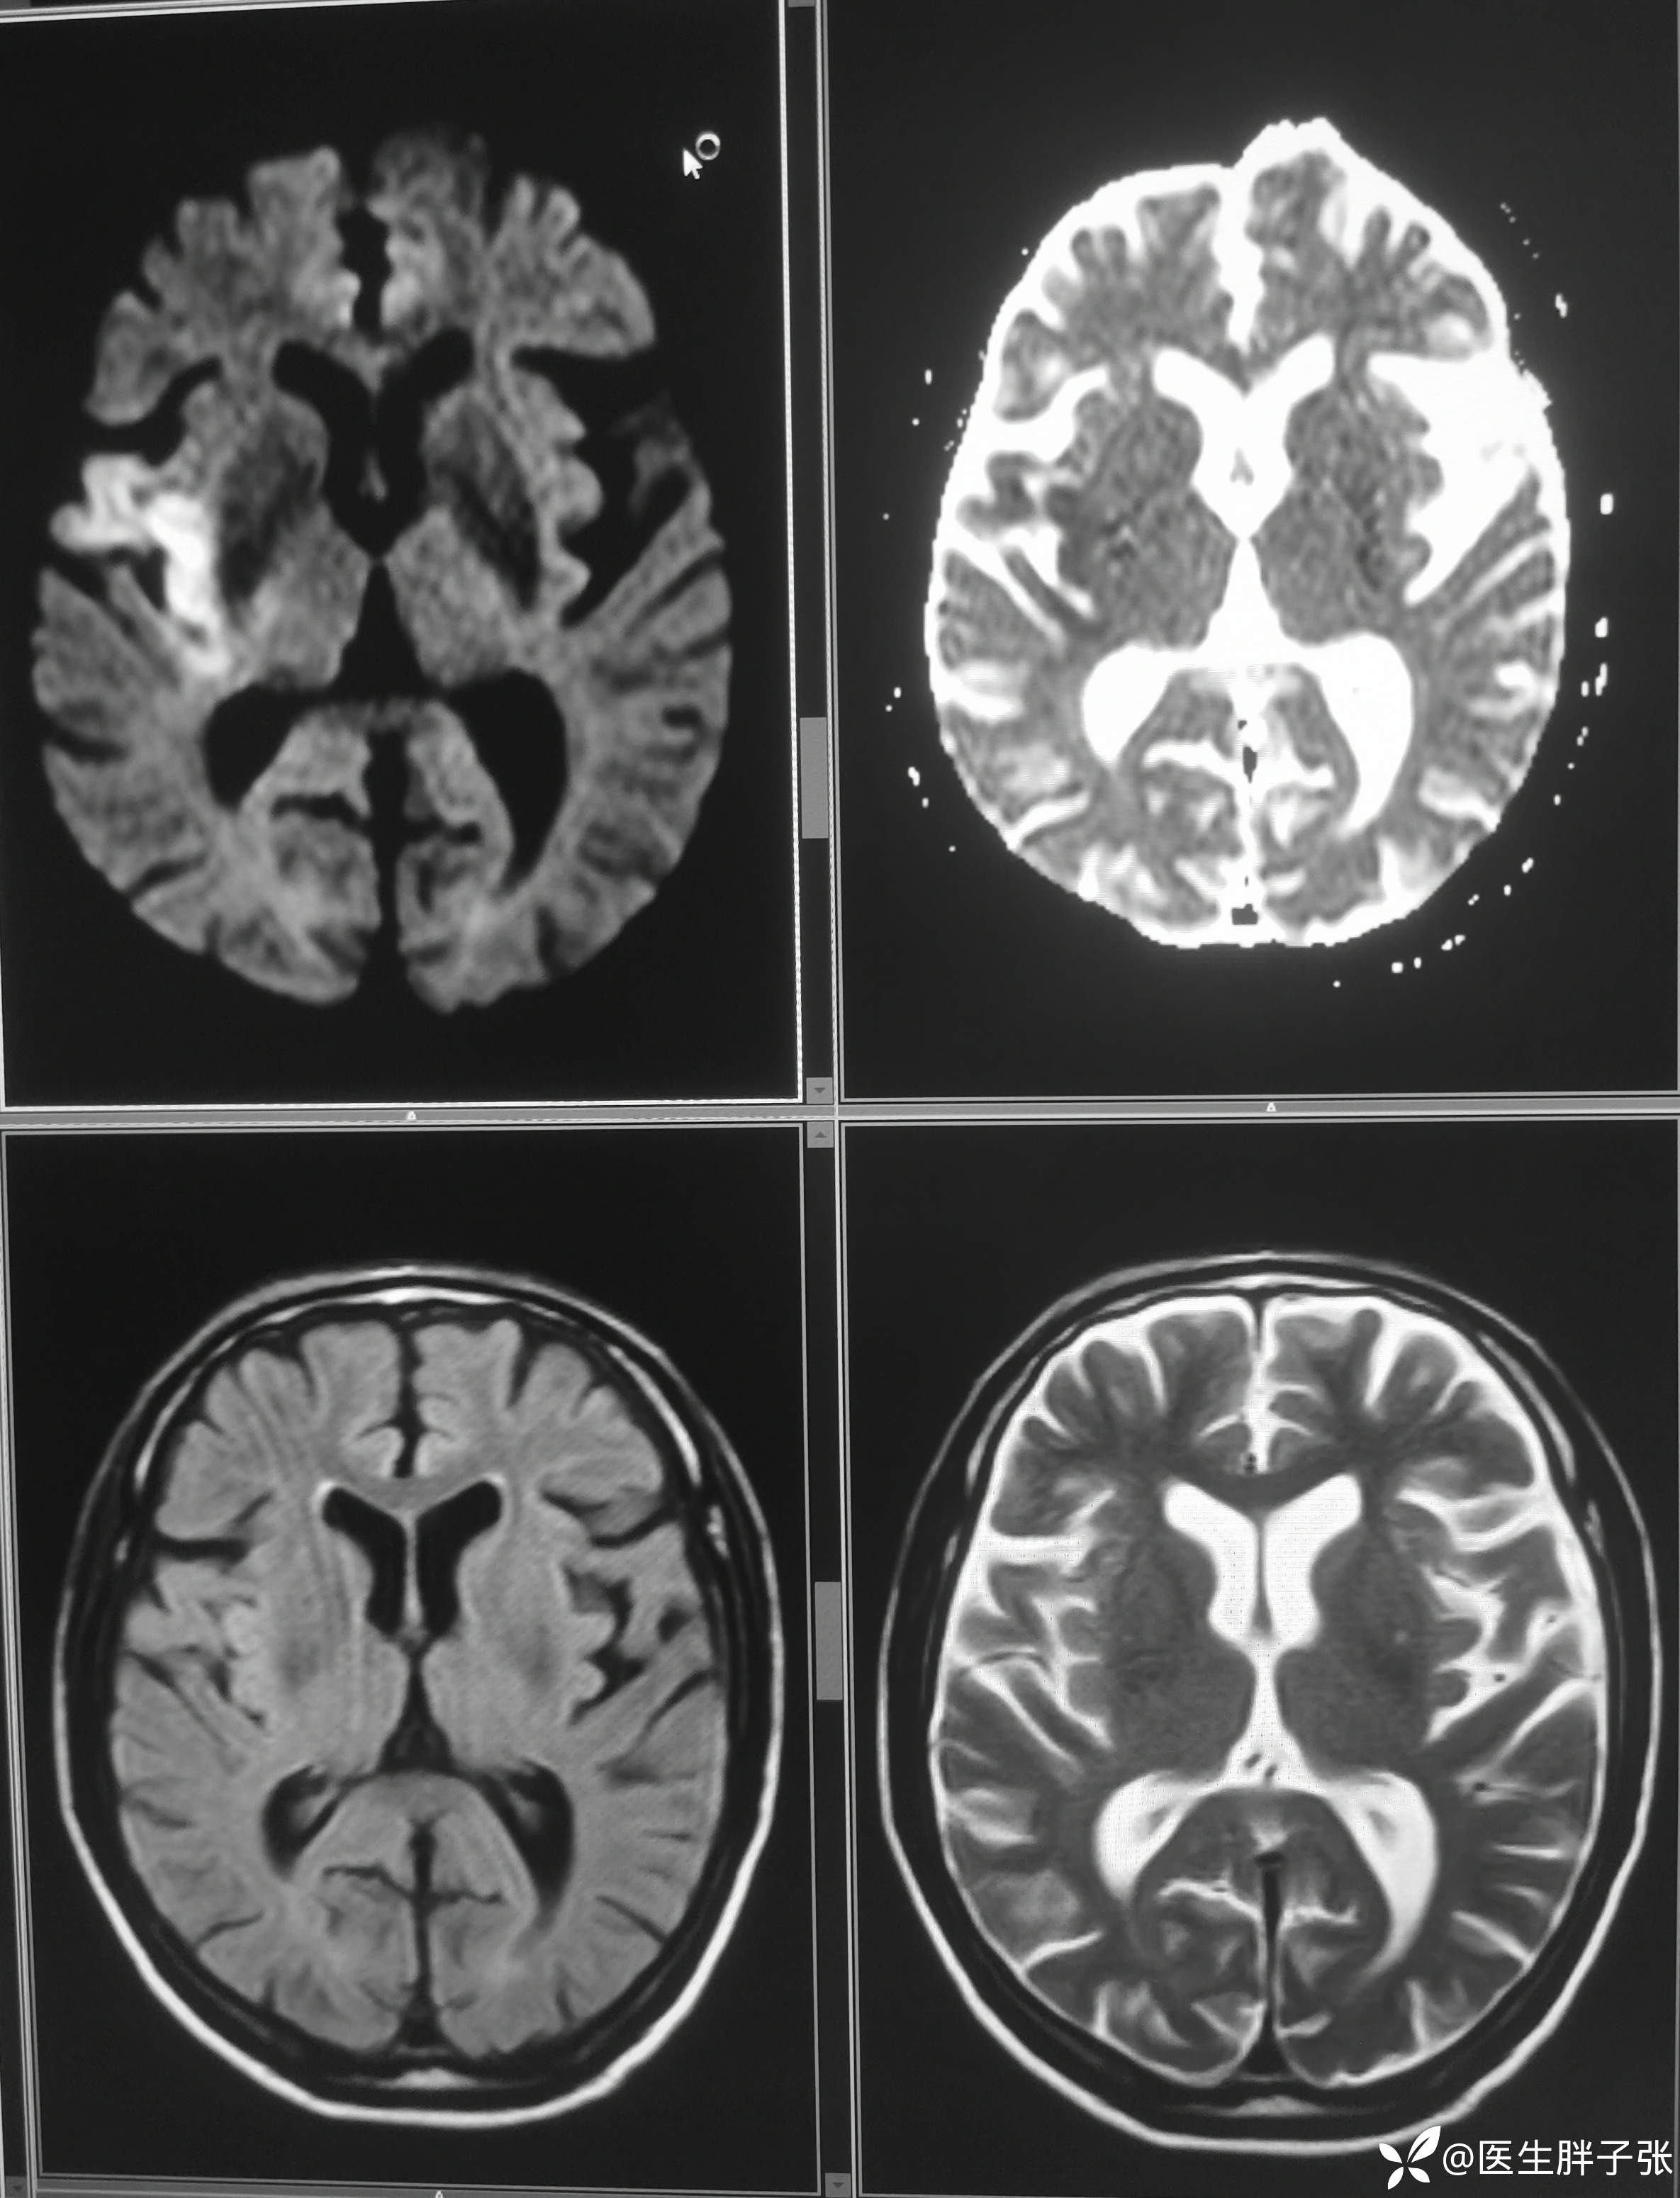

颅脑MR:右侧颞叶新近梗死灶;老年性脑改变;右侧大脑中动脉部分M2段及以远未见显示,建议头颈部CTA检查。

患者为醒后卒中患者,幸运的是恰好晨起交班的时候来院,恰好能查核磁,核磁提示存在DWI-FLAIR错配